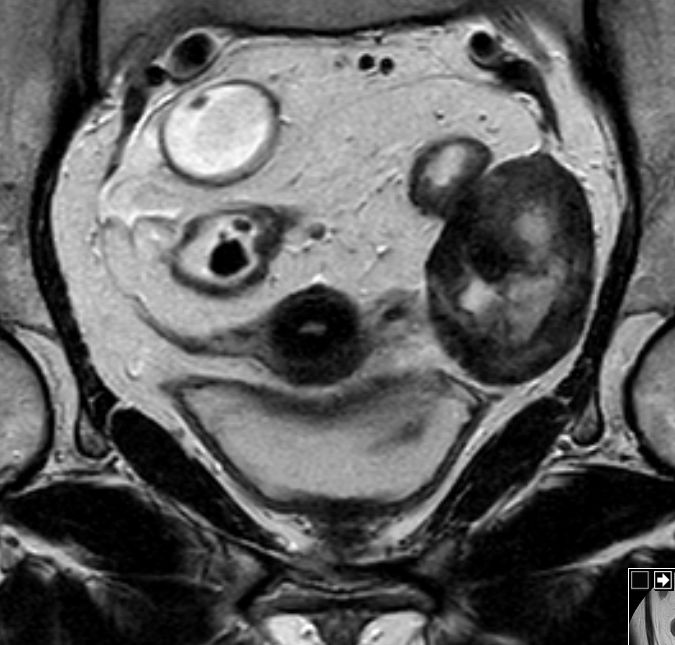

| Fibrom | 62-jährige Frau mit einem Rektumkarzinom und einer

Raumforderung des linken Ovars. ![]() |

Makroskopie: 6,5 x 6 x 4 cm großes Ovar. Es enthält einen 6 cm durchmessenden Knoten.

Dieser mit weißlichen, derben Schnittflächen. Der Knoten ist glatt begrenzt.![]() |

Mikroskopie: Ovar mit einem zellarmen fibrösen Tumor. In Zügen angeordnete Bindegewebsfasern. Keine Zell- und Kernpolymorphie. Keine erhöhte Mitoserate.

Eingelagert einzelne Gefäße. Angrenzendes Ovarialparenchym komprimiert und mit mehreren Corpora albicantia. MRT sT1W TSE![]() |

MRT sT2W TSE![]() | |||

MRT sT2W TSE![]() | ||||